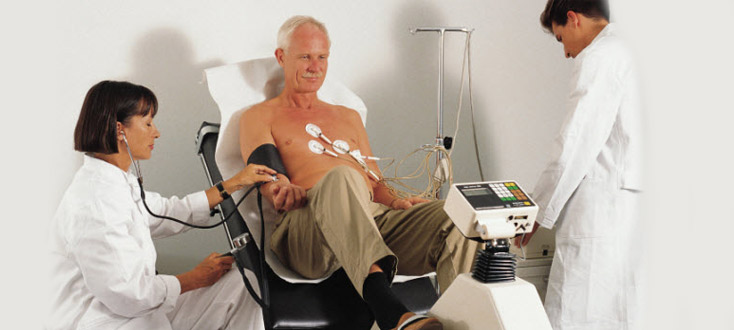

This testing provides information about how your heart works during physical stress. Some heart problems areeasier to diagnose when your heart is working hard and beating fast.During heart exercise testing, you exercise to make your heart work hard and beat fast. Tests are done on your heart while you exercise.You might have arthritis or another medical problem that prevents you from exercising during a this test. If so, our doctor may give you medicine to make your heart work hard, as it would during exercise.